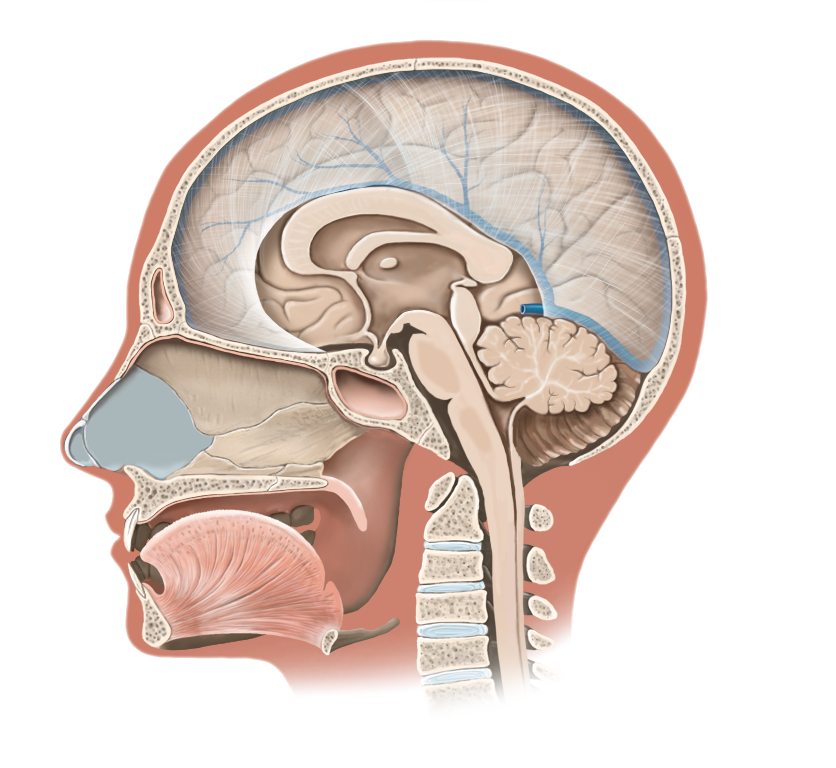

Medical Illustration

All images are works made for hire and are the exclusive property of the client. These are shown as sample purposes of my work only. For licensable work, please see my Illustration Services page.

Medical Illustrator for Precision Graphics, Lachina, and Human Kinetics Publishing (current)

Contract freelancer for many others, some examples of my work below.